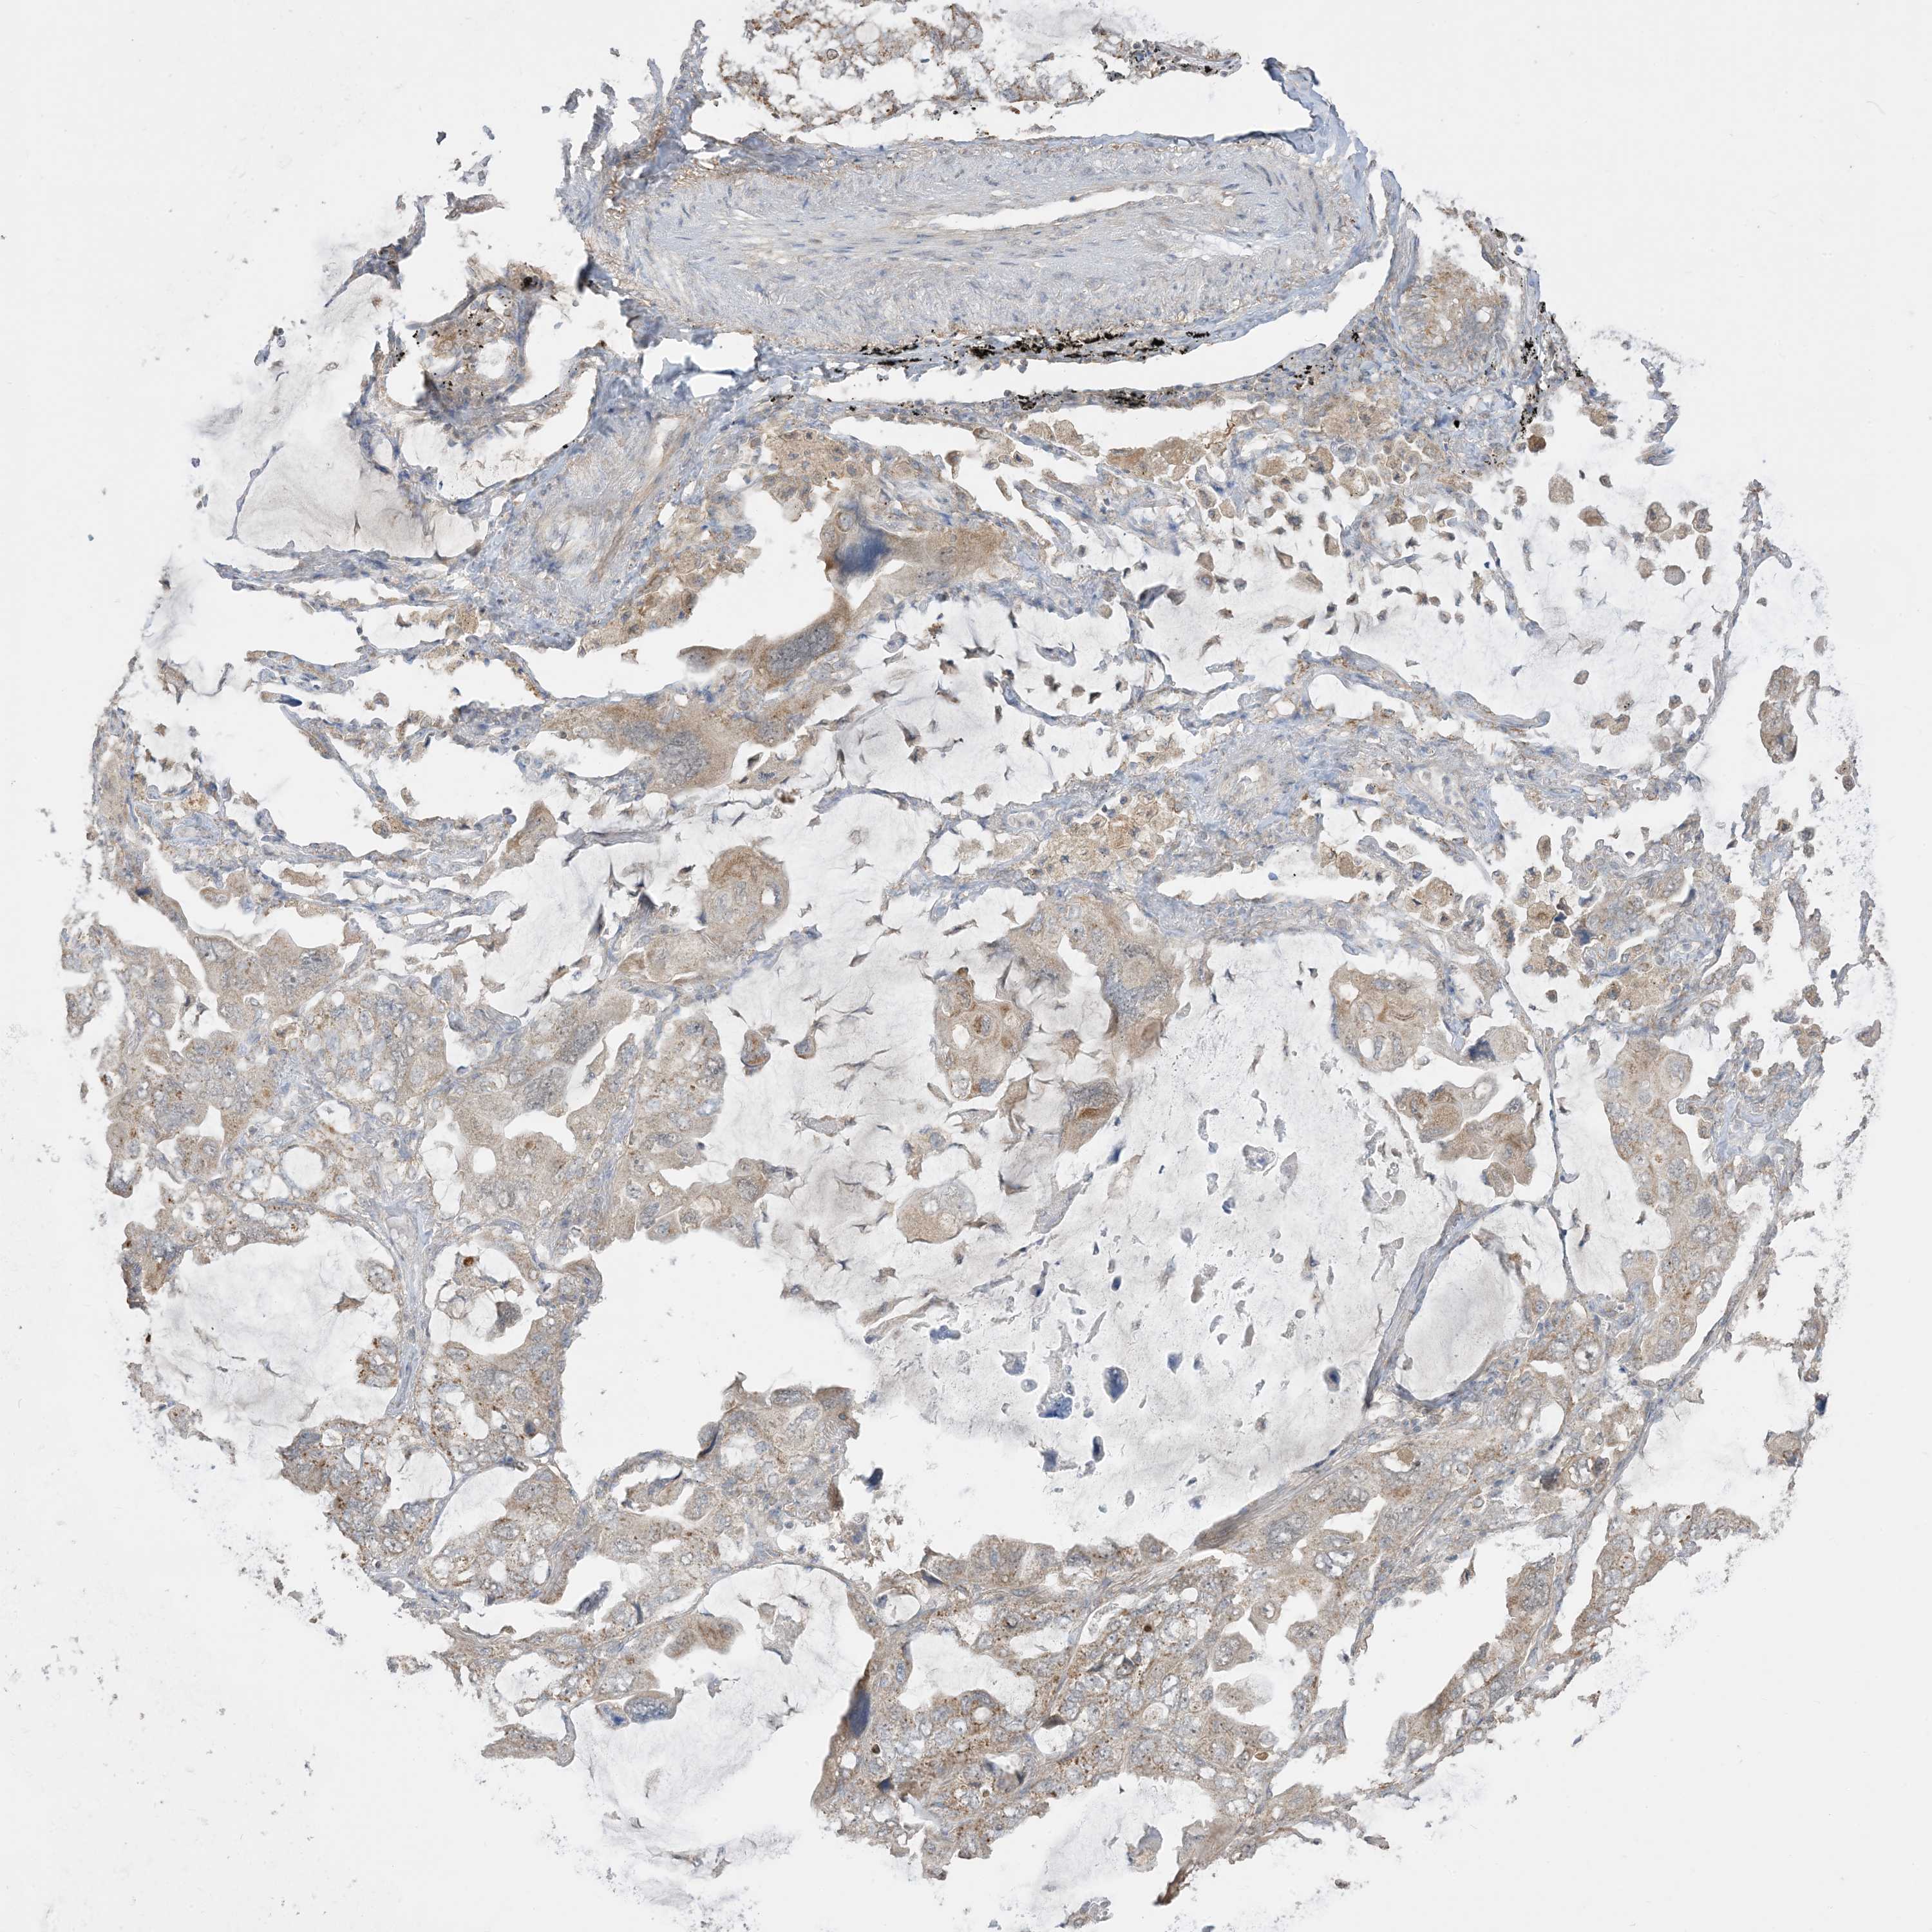

LUNG SQUAMOUS CELL CARCINOMA (TCGA) - Interactive survival scatter ploti

The Survival Scatter plot shows the clinical status (i.e. dead or alive) for all individuals in the patient cohort, based on the same data that underlies the corresponding Kaplan-Meier plots. Patients that are alive at last time for follow-up are shown in blue and patients who have died during the study are shown in red.

The x-axis shows the expression levels (FPKM) of the investigated gene in the tumor tissue at the time of diagnosis. The y-axis shows the follow-up time after diagnosis (years). Both axes are complimented with kernel density curves demonstrating the data density over the axes. The top density plot shows the expression levels (FPKM) distribution among dead (red) and alive patients (blue). The right density plot shows the data density of the survived years of dead patients with high and low expression levels respectively, stratified using the cutoff indicated by the vertical dashed line through the Survival Scatter plot. This cutoff is automatically defined based on the FPKM cutoff that minimizes the p-score. The cutoff can be changed by dragging the vertical line or by entering a cutoff value in the square labeled "Current cut-off".

Under the Survival Scatter plot the p-score landscape (black curve; left axis) is shown together with dead median separation (red curve; right axis). Dead median separation is the difference in median mRNA expression between patients who have died with high and low expression, respectively. It is calculated as follows: median FPKM expression of dead patients with high expression - median FPKM expression of dead patients with low expression. This is intended to aid the user in visually exploring custom cutoffs and the associated p-scores and dead median separation.

Individual patient data is displayed and can be filtered by clicking on one or more of the category buttons on the top of the page. Categories describing expression level and patient information include: high, low, alive, dead, female, male and tumor stages. The scale of the x-axis can be toggled between linear and log-scale by clicking on the "x log" button. Mouse-over function shows TCGA ID, patient information and mRNA expression (FPKM) for each patient.

& Survival analysisi

Kaplan-Meier plots summarize results from analysis of correlation between mRNA expression level and patient survival. Patients were divided based on level of expression into one of the two groups "low" (under cut off) or "high" (over cut off). X-axis shows time for survival (years) and y-axis shows the probability of survival, where 1.0 corresponds to 100 percent.

SIRT3 is not prognostic in Lung Squamous Cell Carcinoma (TCGA)

Best expression cut offi

Based on the FPKM value of each gene, patients were classified into two groups and association between prognosis (survival) and gene expression (FPKM) was examined. The best expression cut-off refers the FPKM value that yields maximal difference with regard to survival between the two groups at the lowest log-rank P-value. Best expression cut-off was selected based on survival analysis .

When clicking on this number, the vertical dashed line indicating cut-off, the interactive survival plot, and the Kaplan-Meier curve will be adjusted to show results based on the best expression cut-off.

: 8.54

Average pTPM 9.5

Number of samples 489